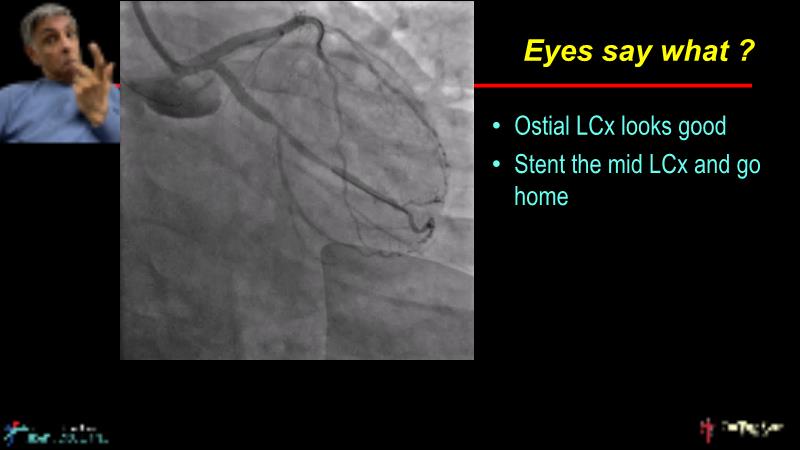

• To understand why the use of IVUS imaging is different from seeing with experienced eyes to achieve improved left main bifurcation outcome